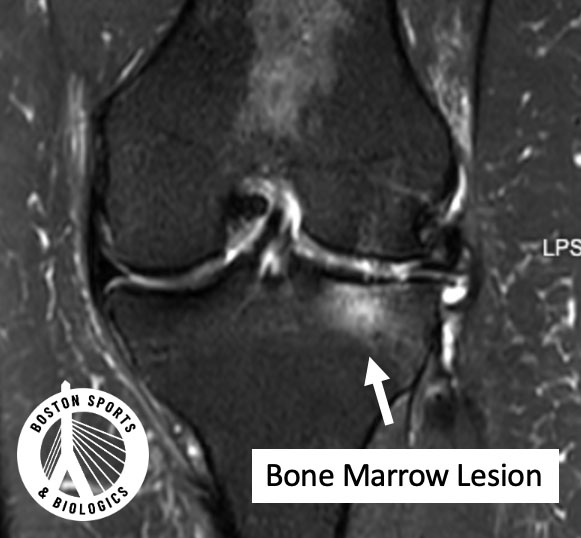

On MRI, a bone marrow lesion appears as an ill-defined bright area in the bone just beneath the cartilage (the subchondral bone). Historically, this was called “bone marrow edema,” implying simple swelling. But research shows it’s more complex than that. Learn more about knee osteoarthritis here.

A landmark MRI–histology study by Zanetti et al. in Radiology found that what we call “bone marrow edema” on MRI is often not primarily fluid. Instead, it commonly contains:

In other words, a BML represents stressed, injured, and actively remodeling bone, not just inflammation.